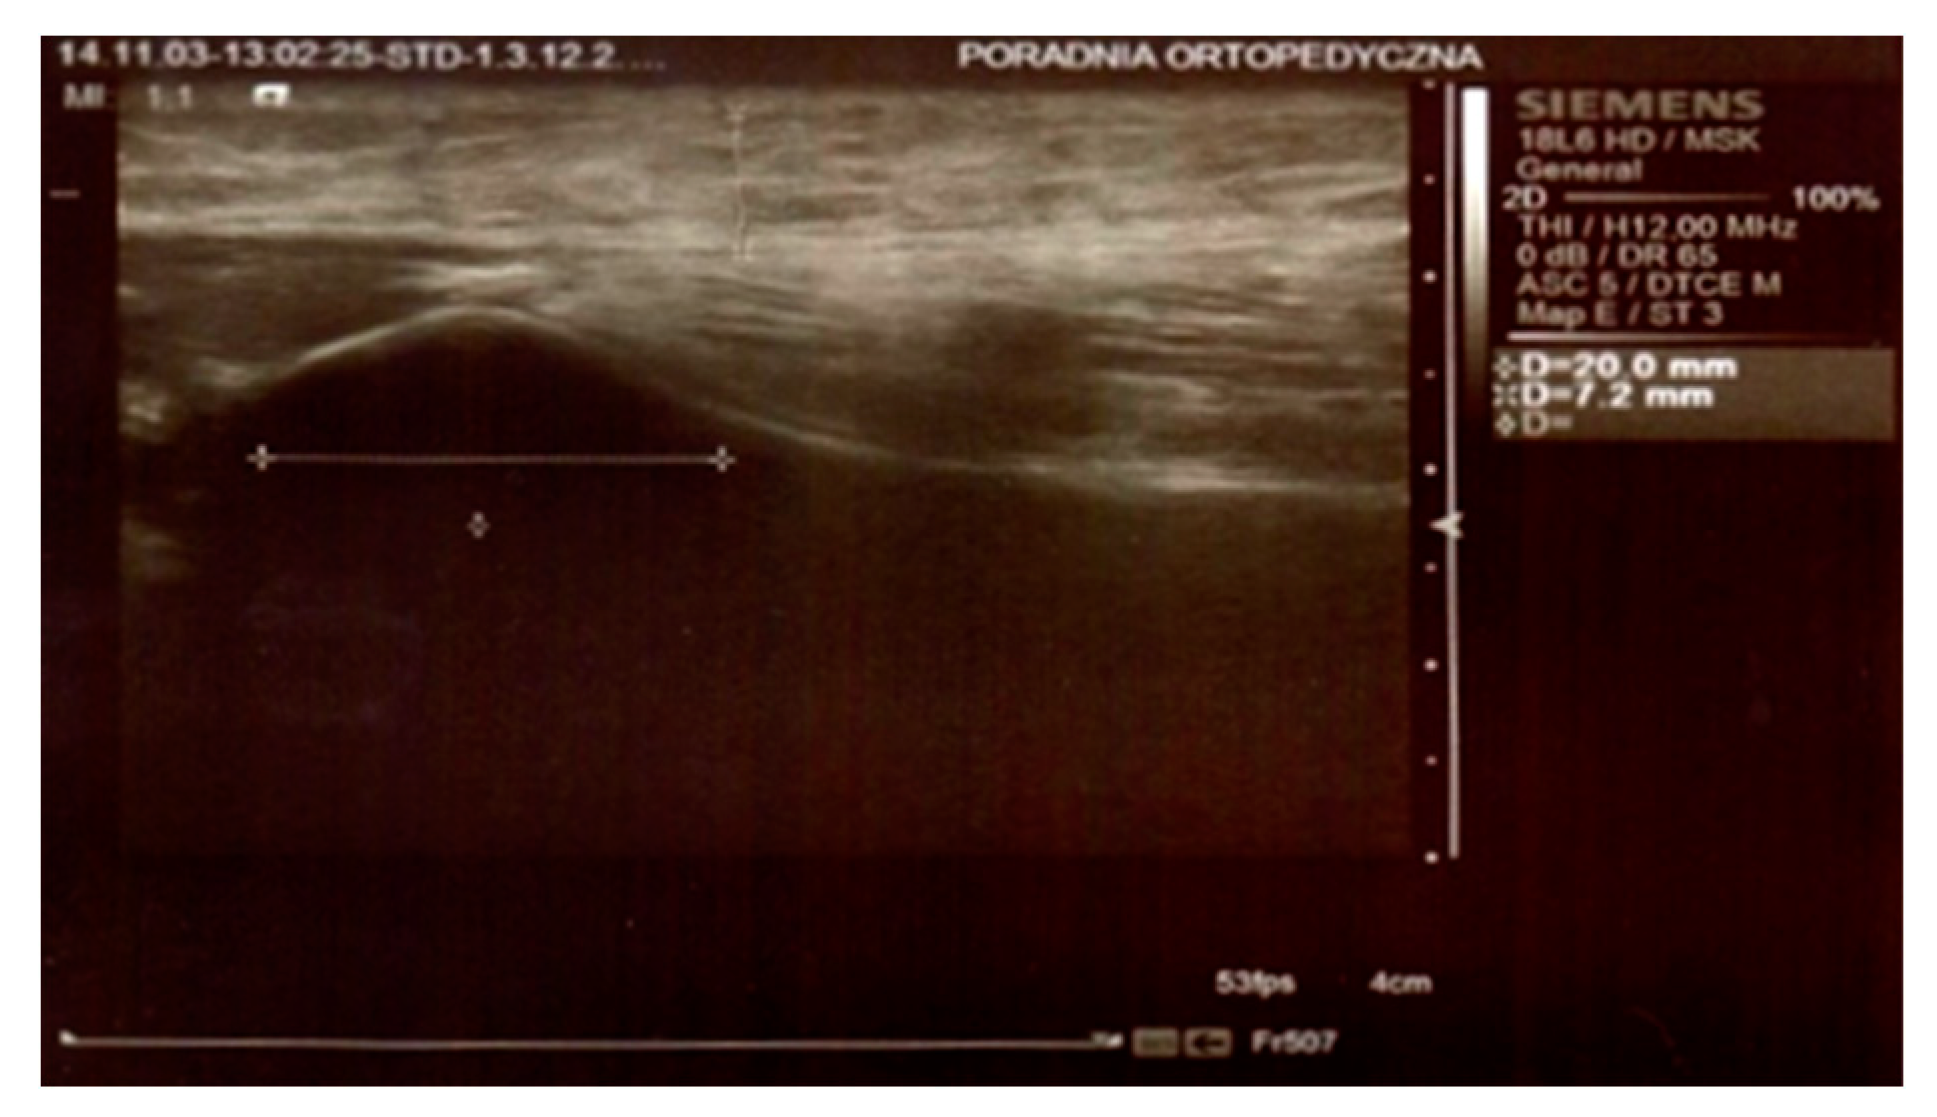

In both groups, on day 3 and 8 after the surgery, the thickness of the swelling was determined by an ultrasound scan by means of Simens ACUSON S2000 HELX EVOLUTION with a 18L6 HD linear head. The parameters were measured at the level of the top of the head of the fibula, 25 mm below the neck of the fibula, and 50 mm below the neck of the fibula on the longitudinal axis of the limb (Figure 1 and Figure 2).

Figure 1. Ultrasound scan. Measurements at the top of the head of the fibula.